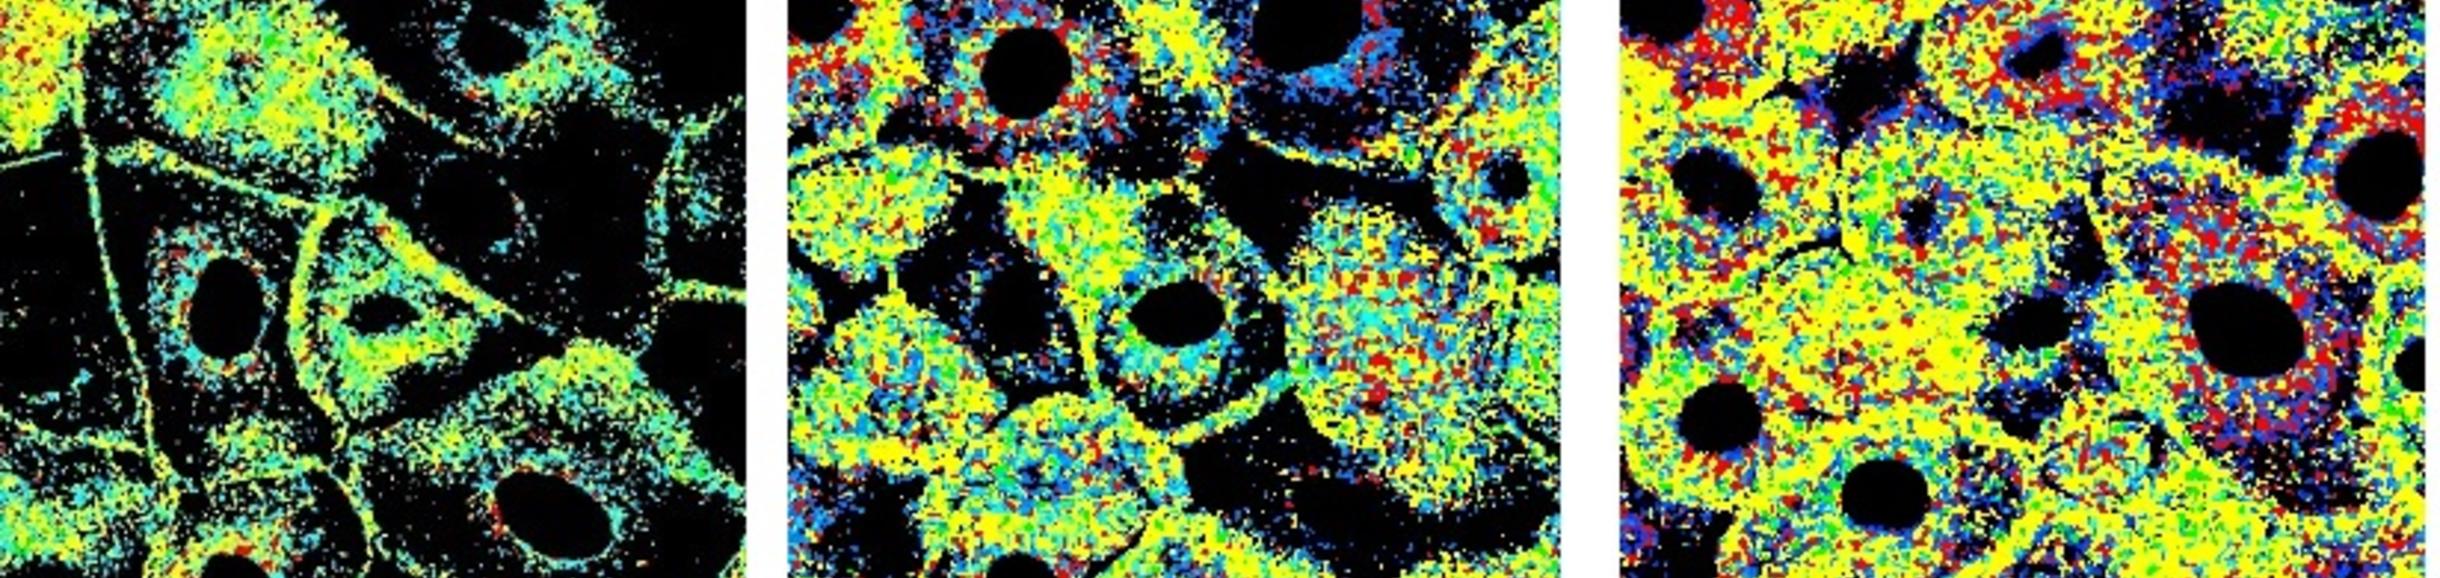

Thirty year academic research career focusing upon photochemistry of intrinsic and extrinsic epidermal chromophores (urocanic acid, UV filters, ROS sensitization) and epidermal environmental conditions (stratum corneum pH, ozone). Developed a two-photon fluorescence lifetime imaging methodology to visualize the stratum corneum pH gradient. Visualization of UV induced ROS as a function of epidermal depth and keratinocyte location using fluorescence microscopy techniques. Identified conditions by which FDA-approved UV filters can sensitize ROS in individual epidermal layers above intrinsic epidermal levels.

•  Discovered that commonly used sunscreens can generate highly destructive reactive oxygen species in epidermis.

•  Showed that antioxidants used in topical skin formulations reduce the number of ROS in both anucleated and nucleated epidermal layers.